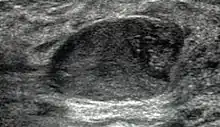

Fibroadenoma in ultrasound

A fibroadenoma is usually diagnosed through clinical examination, ultrasound or mammography, and often a biopsy sample of the lump.[9] Suspicious findings on imaging may result in a person needing a biopsy in order to gain a definitive diagnosis. There are three types of biopsies: fine-needle aspiration, core-needle biopsy and surgical biopsy. The method of biopsy depends on the appearance, size and location of the breast mass.[10]

The FDA approved cryoablation of a fibroadenoma as a safe, effective, and minimally-invasive alternative to open surgical removal in 2001.[27] During cryoablation, ultrasound imaging is used to guide a probe into the mass of breast tissue. Extremely cold temperatures are then used to destroy the abnormal cells, and over time the cells are reabsorbed into the body.[28] The procedure can be performed as an outpatient surgery using local anesthesia, and leaves substantially less scarring than open surgical procedures and no breast tissue deformation.